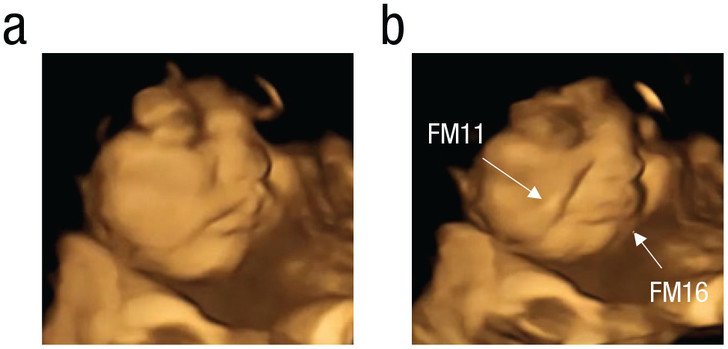

Було проведено 4D-ультразвукове сканування вагітних жінок, щоби побачити, як ненароджені діти гримасували від різних продуктів, які їли їхні матері.

У дослідженні брало участь 100 вагітних жінок віком від 18 до 40 років. Ним провели 4D-УЗД на 32-му та 36-му тижні вагітності. Жінкам давали одну капсулу за 20 хвилин до сканування. В одній було або 400 мг моркви, або 400 мг порошку капусти.

І водночас кривилися, коли мами вибирали капусту кале. Навіть невеликої кількості моркви або капусти було достатньо, щоб спричинити реакцію у плода.

Плід, який «скуштував» капусту. Фото: journals.sagepub.com